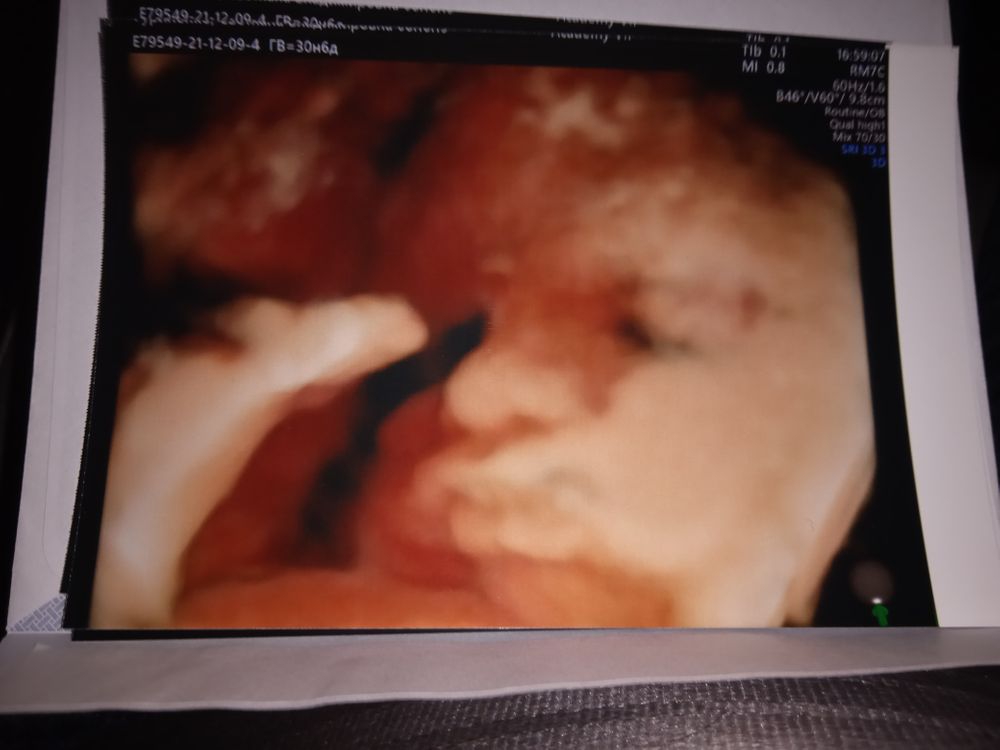

Лучше всего личико видно, когда ещё много околоплодных вод, 21-23 недели должно быть ещё норм. Я не помню, на каком сроке прошлый раз была, но вот в 31 неделю уже толком не посмотришь, т.к. тесновато, у него то ручки перед лицом, то пуповина, то в матку упёрся мордашкой

Почти 31 неделька и 21 неделька